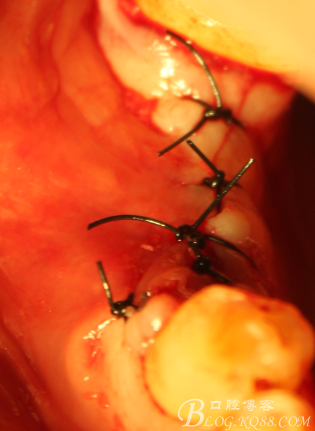

C6頰側填入自體骨,嚴密縫合關閉創(chuàng)口

切開,成骨情況良好,

搔刮C5頸部肉芽

上愈合基臺,間斷縫合關閉創(chuàng)口,頰側牙齦部分恢復形態(tài)